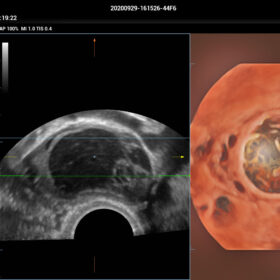

- HD-Scope – improving diagnostic confidence of minor lessions

- Smart Scene 3D – Full Stack smartness obstetric solution empowered by ZST+. Comprehensive 3D/4D OB imaging solution with comprehensive fetal parts coverage.

One Key for favorite fetal part imaging, reducing manual adjustment - Smart Face – Automatic removal of occlussions over fetal face with one click